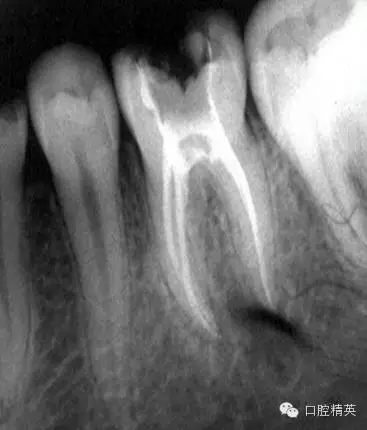

在根管治療的幾年經(jīng)驗(yàn)中,有些感悟愿與朋友們分享,不到的地方請(qǐng)同仁指正。在做好根管治療時(shí)我們首先要攝片分析根管難度選擇合適器具合適方法進(jìn)行治療,根管難度評(píng)估:簡(jiǎn)單根管(5-10度)

,中等難度根管,(10-25度)復(fù)雜難度根管(大于25度)

3復(fù)雜根管